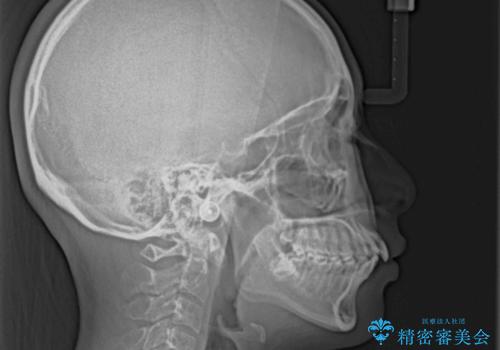

- 前歯部のデコボコと口元が出ているのが気になるとのことで来院された患者様です。

口元の突出感の解消と、このままデコボコを解消するとさらに出っ歯傾向になってしまうことを考慮し、上下左右の小臼歯を抜歯しクリアブラケットにて矯正していくこととしました。